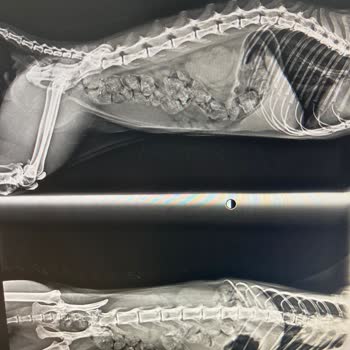

Ordu Bahçelievler Veterineryam Kliniği’nin sokakta yaşayan yaklaşık 4–5 aylık iki yavru kediye çok erken yaşta kısırlaştırma işlemi yapıp tekrar sokağa salması nedeniyle şikayetçiyim. Bu işlem yaklaşık 1 ay önce yapıldı ve kedilerin her ikisi de kısa süre içinde hastalanarak öldü. Durumu sorduğumda...